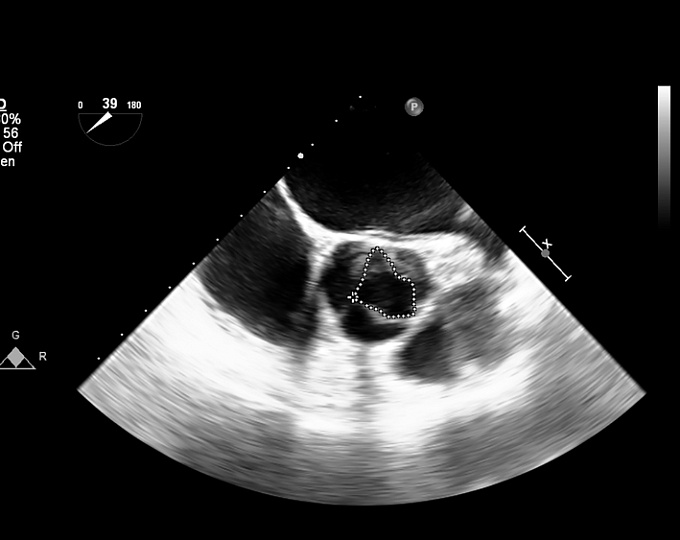

Существует ли связь между нарушениями сна и риском аортального стеноза?

Целью исследования было оценить связь между нарушениями сна и риском развития аортального стеноза.

• Показано, что нарушения сна ассоциированы с повышением риска аортального стеноза на 15% (коэффициент рисков, 1,15 95% доверительный интервал: 1,13–1,18).

• Эта связь отчасти объяснялась дислипидемией

Нарушения сна ассоциированы с повышением риска аортального стеноза. Дислипидемия, наблюдающаяся при нарушениях сна, частично объясняет повышение риска.